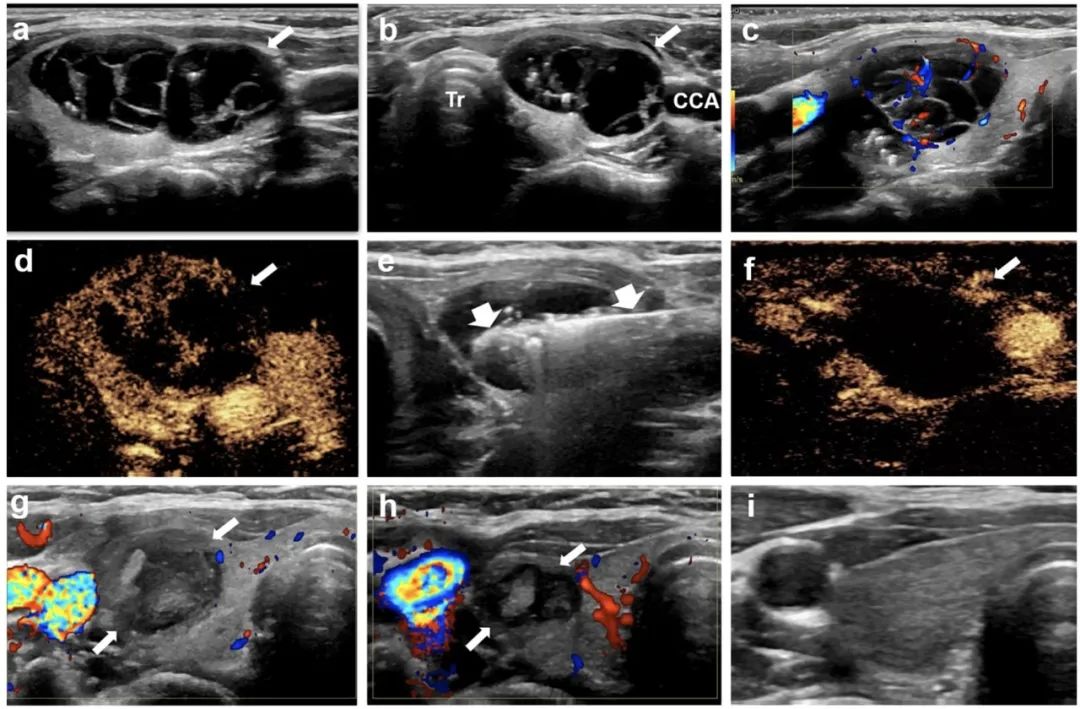

甲狀腺左葉實性結節(jié),微波消融4年后結節(jié)明顯縮小

甲狀腺右葉囊性為主結節(jié),微波消融后3年,病灶完全消失